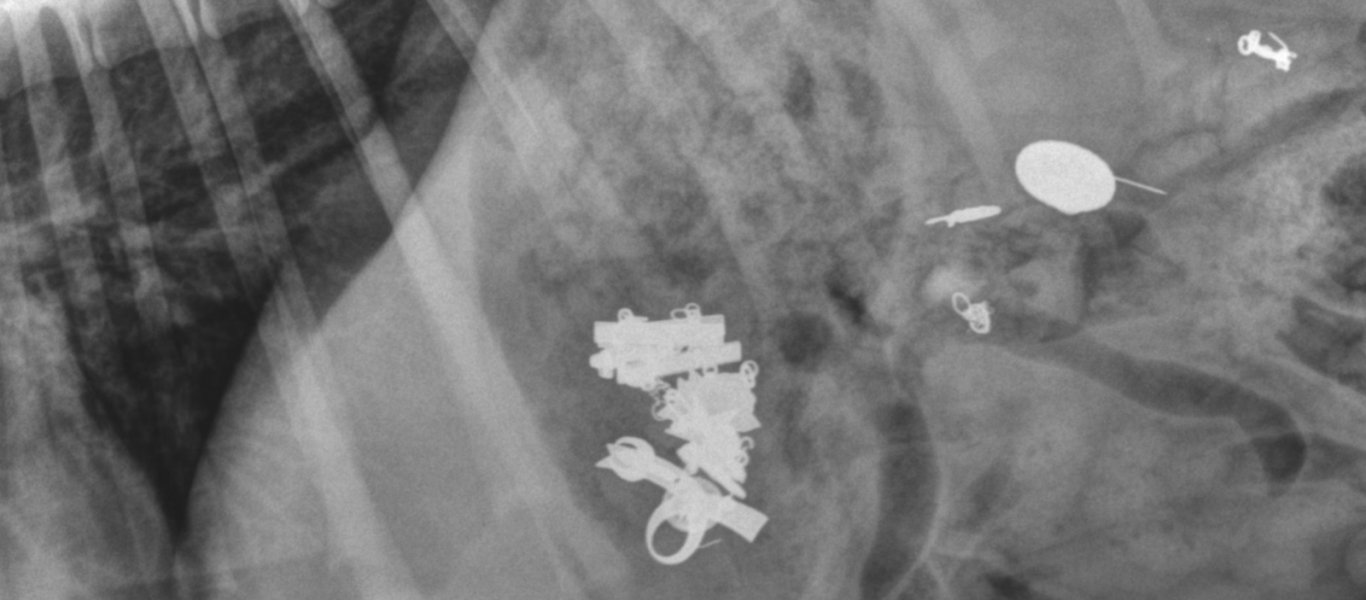

Περισσότερα από 100 μεταλλικά αντικείμενα και κομμάτια μετάλλου σε διάφορα μεγέθη αφαίρεσαν χειρουργοί στη Γαλλία από το στομάχι ενός 52χρονου άνδρα ο οποίος τα είχε καταπιεί. Ο άνδρας έκανε αντιψυχωσική θεραπεία με φαρμακευτική αγωγή, όμως συνέχιζε να έχει την τάση να καταπίνει μεταλλικά αντικείμενα, όπως κουταλάκια, νομίσματα, καρφιά, βίδες, μικρά μαχαίρια, μεταλλικά ξυραφάκια και άλλα.

Σταδιακά ορισμένα μεταλλικά αντικείμενα, που είχαν χωνευθεί μόνο εν μέρει ή καθόλου, είχαν σχηματίσει ενιαίες μεταλλικές μάζες μέσα στο στομάχι του, τόσο μεγάλες που είχαν φράξει τον πυλωρό, το στόμιο που συνδέει το στομάχι με το λεπτό έντερο, πράγμα που εμπόδιζε το άδειασμα του στομαχιού του από το περιεχόμενό του.

Ο άνδρας είχε πάει πέντε φορές στα επείγοντα περιστατικά των νοσοκομείων σε διάστημα πέντε ετών, παραπονούμενος για στομαχόπονους, ναυτίες και εμετούς με αίμα. Σε τέσσερις περιπτώσεις οι γιατροί χρειάσθηκε να τον εγχειρίσουν για να αφαιρέσουν μεταλλικές μάζες από το στομάχι του, κάτι που δεν ήταν δυνατό να γίνει μόνο με το ενδοσκόπιο.